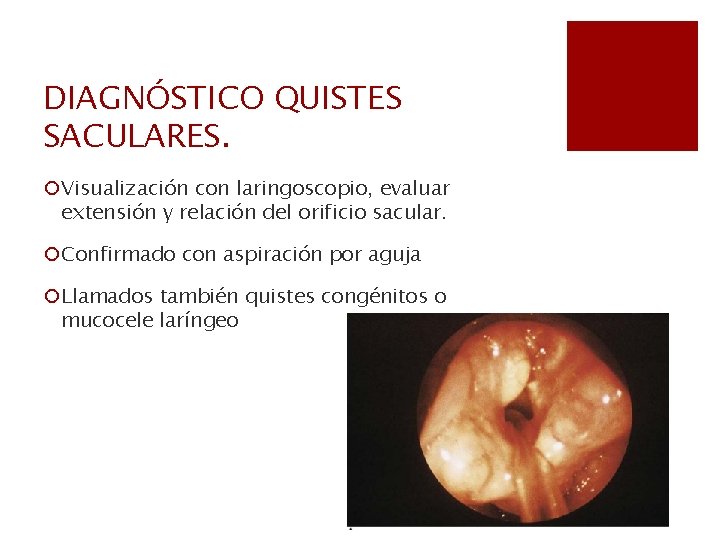

DIAGNÓSTICO QUISTES SACULARES. ¡Visualización con laringoscopio, evaluar extensión y relación del orificio sacular. ¡Confirmado con aspiración por aguja ¡Llamados también quistes congénitos o mucocele laríngeo